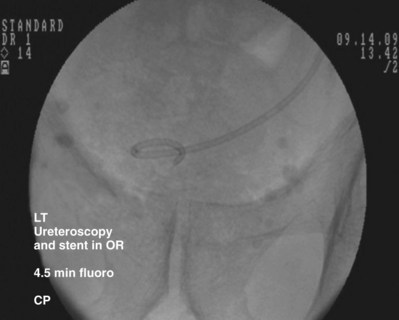

An alternative technique that relies more on fluoroscopic visualization for stent placement and less on cystoscopic visualization is often advantageous when dealing with more challenging stent placements such as impacted ureteral stones or malignant obstruction (Figs. 7-7 through 7-16).

Figure 7–7 Flexible cystoscopy is used to locate and, under fluoroscopic guidance, pass a floppy tip guidewire through the ureteral meatus.

After obtaining bladder access with either a flexible or rigid cystoscope, a floppy-tip guidewire is advanced into the ureteral meatus and coiled in the renal pelvis using fluoroscopy, the cystoscope is then removed and an 8- to 10-Fr coaxial dilator is advanced under fluoroscopy until the 10-Fr sheath is at the urethral meatus. The 8-Fr internal dilator is removed, leaving a conduit (10-Fr outer sheath) through which to advance the stent.

The ureteral stent is then advanced over the guidewire through the 10-Fr sheath by using a pusher with a small fluoroscopically visible metal band at its tip. The metal tip pusher is advanced under fluoroscopic control to the upper border of the pubic symphysis in male patients and lower border in female patients, while stabilizing the position of the lower end of the stent. The 10-Fr sheath and subsequently the guidewire are removed, allowing the stent to curl in the bladder.